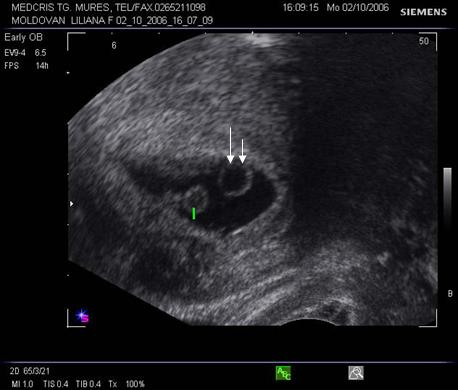

Fig nr 39

Prezinta aceeasi sarcina biamniotica bichoriala,ca in figura precedenta, cu

semnul lambda marcat cu sageata